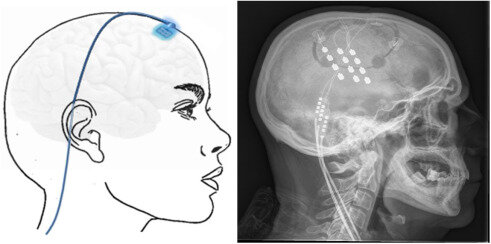

• Técnicas de estimulación profunda

Técnicas de estimulación profunda

Implantación de electrodos cerebrales que buscan modificar conductas a través de un estimulador, se usa con fines curativos por ejemplo en el parkinson, TOC, e incluso problemas visuales. (UNIR, La Universidad en Internet. 202, min, 28).